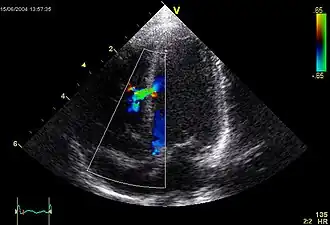

L'échocardiographie-doppler

En pratique, l'échocardiographie doppler, examen non douloureux et non irradiant suffit pour poser un diagnostic précis de la malformation et sauf exception pour apprécier son retentissement et sa gravité. L'image ci-contre nous montre une turbulence sanguine (en vert) traversant la paroi inter ventriculaire (ligne verticale en gris), et allant d'un ventricule à l'autre (cavités ventriculaires en noir). Le doppler permet de quantifier le shunt (calcul du rapport du débit systémique sur débit pulmonaire). Cet examen permet également de détecter des anomalies cardiaques associées, d'évaluer le retentissement sur le ventricule droit et d'estimer les pressions des cavités cardiaques droites.